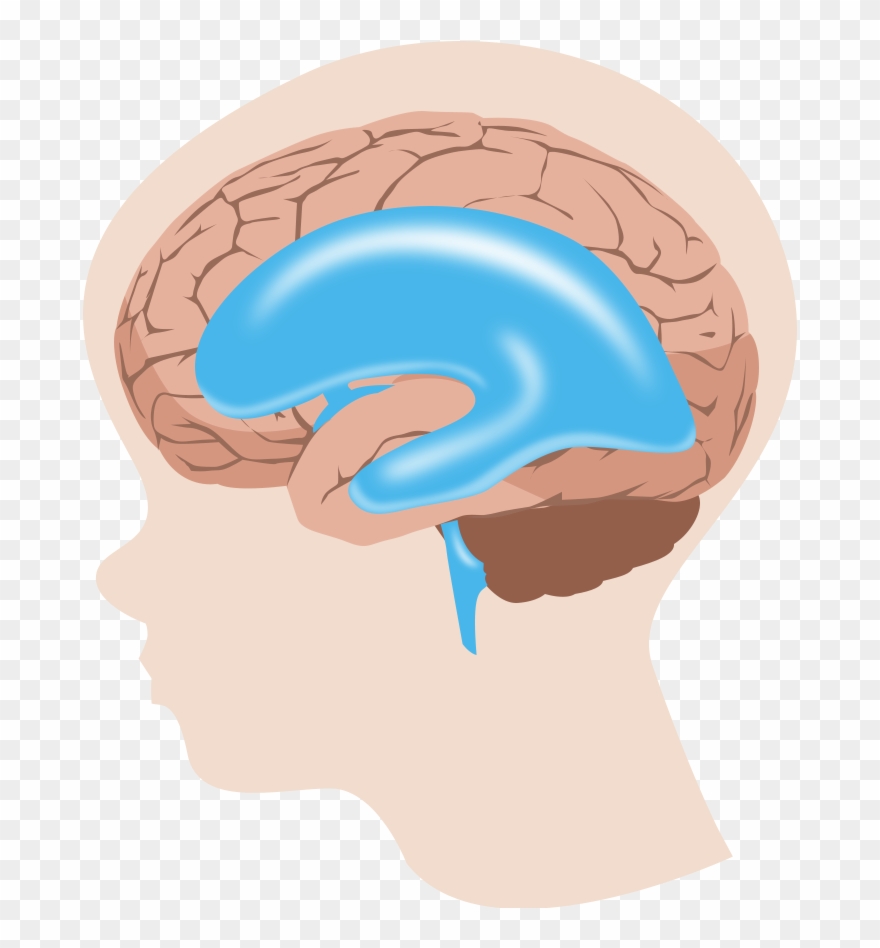

Hydrocephalus

Symptoms And Causes Of Hydrocephalus

Hydrocephalus : Symptoms, Picture, Causes, and Treatment

Hydrocephalus: Causes, Picture, Symptoms And Treatment